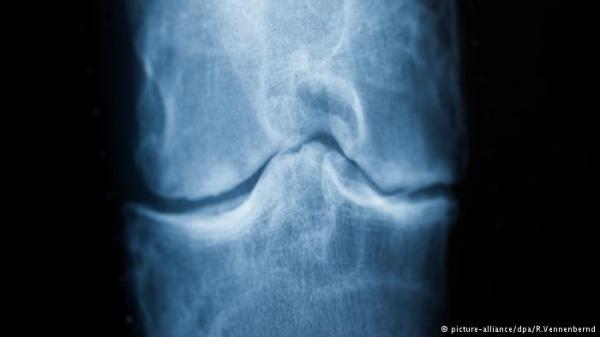

يزداد الفصال العظمي، أحد الأمراض الروماتيزمية، حدة بدرجة كبيرة كلما تقدمنا في السن. ويعتبر الفصال العظمي من أكثر أمراض العظام انتشارا، وهو تلف غير قابل للتجديد يصيب الأنسجة الغضروفية المفصلية التي تعمل على تقليل الاحتكاك الناتج عن حركة المفاصل الدائمة وبالتالي حماية العظام.

ومع تطور الفصال العظمي من الدرجة الخفيفة إلى المعتدلة ثم الحادة تظهر على المصابين أعراض مثل الألم في المفصل المصاب وتقييد حركته وتراكم السوائل فيه وانتفاخه وتورمه. والأمر لا يبقى عند هذا الحد فقد أظهرت دراسة لبحث نُشر في دورية الأبحاث والرعاية الخاصة بالتهاب المفاصل أن المشاكل النفسية ومنها القلق والاكتئاب تفسر جزئيا السبب وراء زيادة احتمالات إصابة مرضى التهاب المفاصل الروماتويدي بأزمات قلبية.

بالإضافة إلى ذلك يتسبب مرض الفصال العظمي المزمن في فقدان وظيفة المفصل وتقييد الحركة ما يتسبب في نهاية الأمر في العجز للمريض.